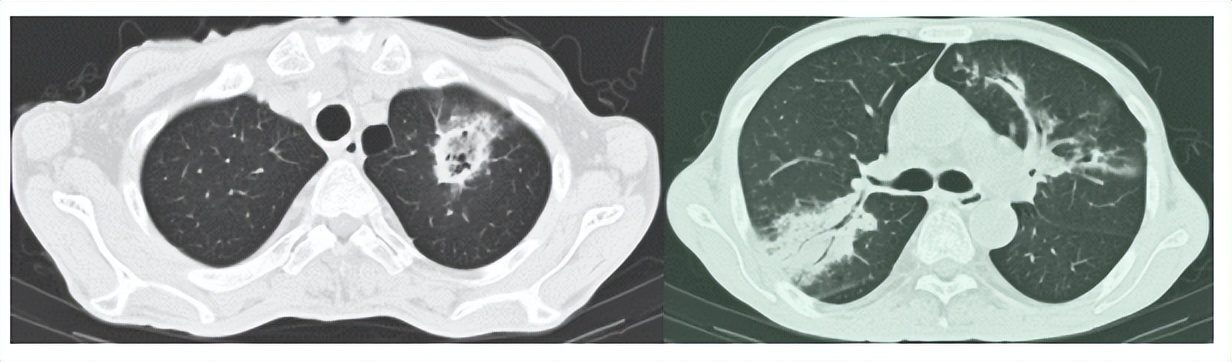

胸部CT检查提示:双肺多发感染性病变;

△左图:胸部CT示左上肺病灶内见反晕征 右图:胸部CT见右上肺实变伴支气管充气征